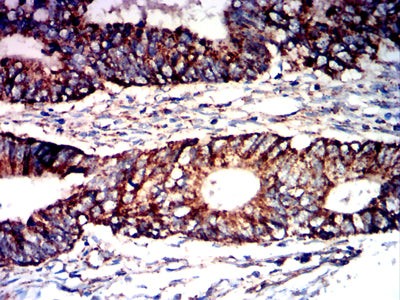

Immunohistochemical analysis of paraffin-embedded human rectal cancer tissues using PNAD mouse mAb with DAB staining.